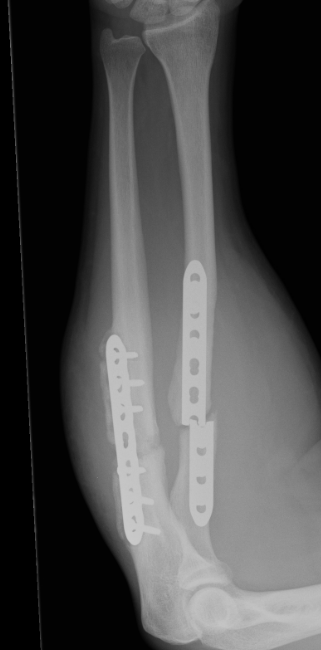

ORIF with DCP plates

Fixation with DCP plates

Radial fracture malunion requiring corrective osteotomy